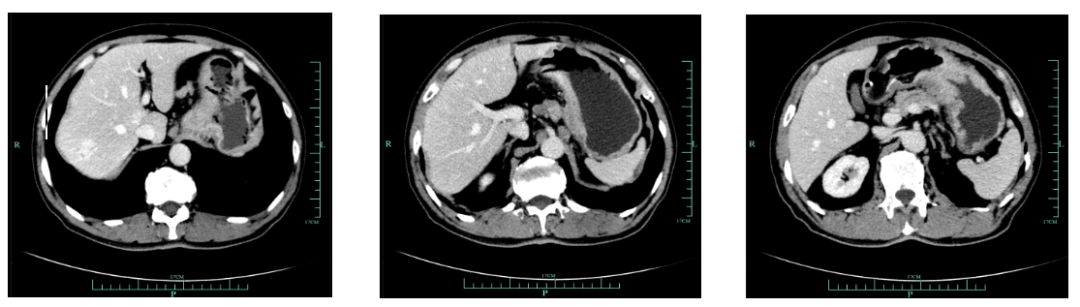

现病史:1月余前出现吞咽哽噎,无饮水呛咳,偶感腹胀腹痛,无恶心呕吐等不适,至外院就诊,上腹部增强CT(2018-12-14)提示:胃小弯及贲门壁异常,提示胃癌。胃周多发肿大淋巴结转移考虑。

既往史(续):全腹部CT平扫+增强提示胃贲门部及体部胃壁增厚,结合临床考虑胃癌伴胃周及腹膜后多发淋巴结转移;肝脏多发血管瘤。

2018-12-20至2019-2-21,SOX Q3W 4周期,具体为奥沙利铂230mg D1,替吉奥3# BID D1-14 ,疗效评估为缩小的SD。